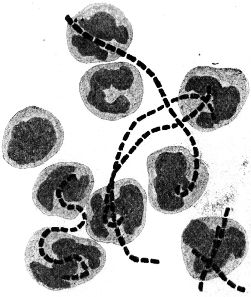

Sehr vieles sprach zugunsten der ersteren Anschauung; vor allem entsprach sie den Erfahrungen, die bei der Erforschung der lebenden Wesen unserer Erde bis dahin gesammelt waren. Der einwandfreie Nachweis ihrer Richtigkeit stieß aber auf eine sehr große Schwierigkeit: fast überall, wo wir in der Natur Bakterien in größeren Mengen begegnen, finden wir verschiedene, ja meist sogar sehr zahlreiche verschiedene Formen in buntem Durcheinander; z. B. treffen wir in einem Tröpfchen Zahnschleim regelmäßig kurze und lange, dünnere und dickere Stäbchen und Schrauben, daneben kleinere und größere[5] Kugelbakterien miteinander vermengt (vgl. Abb. 2). Es war so gut wie unmöglich, an solchen Bakteriengemischen einwandfreie Beobachtungen über die Fortpflanzungsweise der Bakterien zu machen. So ist es verständlich, daß über diese Frage die Ansichten lange Zeit auseinandergingen.

Bei einiger Übung werden wir aber bald erkennen, daß wir ein Kugelbakterium, ein Stäbchen- oder ein Schraubenbakterium vor uns haben. Mit wachsender Übung vermögen wir – unter Umständen auf den ersten Blick – besonders charakteristische Bakterienarten zu erkennen. Anderseits können wir bei sorgfältiger Beobachtung feine Unterschiede der Formen unter den Angehörigen der drei Grundtypen bald auffinden: so weichen z. B. manche Mikrokokken ein klein wenig von der Kugelgestalt ab, sie sind ein wenig abgeplattet; eine andere Art ist ein klein wenig längsoval, usf. Zur[13] Unterscheidung der Kugelbakterienarten, die im allgemeinen der Eigenbewegung ermangeln, kann uns auch die Art ihrer Lagebeziehungen im hängenden Tropfen wichtige Dienste leisten. Manche Arten bilden in einer Kultur regelmäßig perlschnurartige, kürzere oder längere, 3 bis 5, ja bis 30 und mehr einzelne Glieder aufweisende Ketten (Kettenkokken oder Streptokokken, vgl. Abb. 28, 29). Andere dagegen lagern sich zu weintraubenförmigen Häufchen zusammen und werden danach als Staphylokokken (ἡ σταφυλή die Weintraube) bezeichnet (vgl. Abb. 26). Zwischen den verschiedenen Arten der Stäbchen- und Schraubenbakterien bestehen ferner Unterschiede nach der Länge und Dicke und nach dem Verhältnis des Längen- zum Dickendurchmesser: so begegnen wir langen und schlanken, langen und plumpen, kurzen und schlanken, kurzen und plumpen Stäbchen- und Schraubenformen. Wenn wir sie genau betrachten, so können wir oft noch weitere feine Unterschiede zwischen den verschiedenen Arten erkennen: die einen besitzen abgerundete Enden, die anderen kantige, manche zeigen die Neigung, dadurch, daß mehrere Individuen aneinander haften, Fäden zu bilden, und so gibt es noch eine ganze Reihe feiner Gestaltmerkmale, die der sorgfältige Beobachter zu berücksichtigen hat.